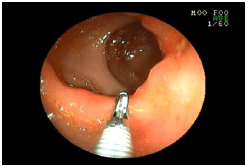

![]() |

ヒモをつかんで回収しているところです。 ヒモを無事に取り出した後、猫は元気に帰宅しています。 |